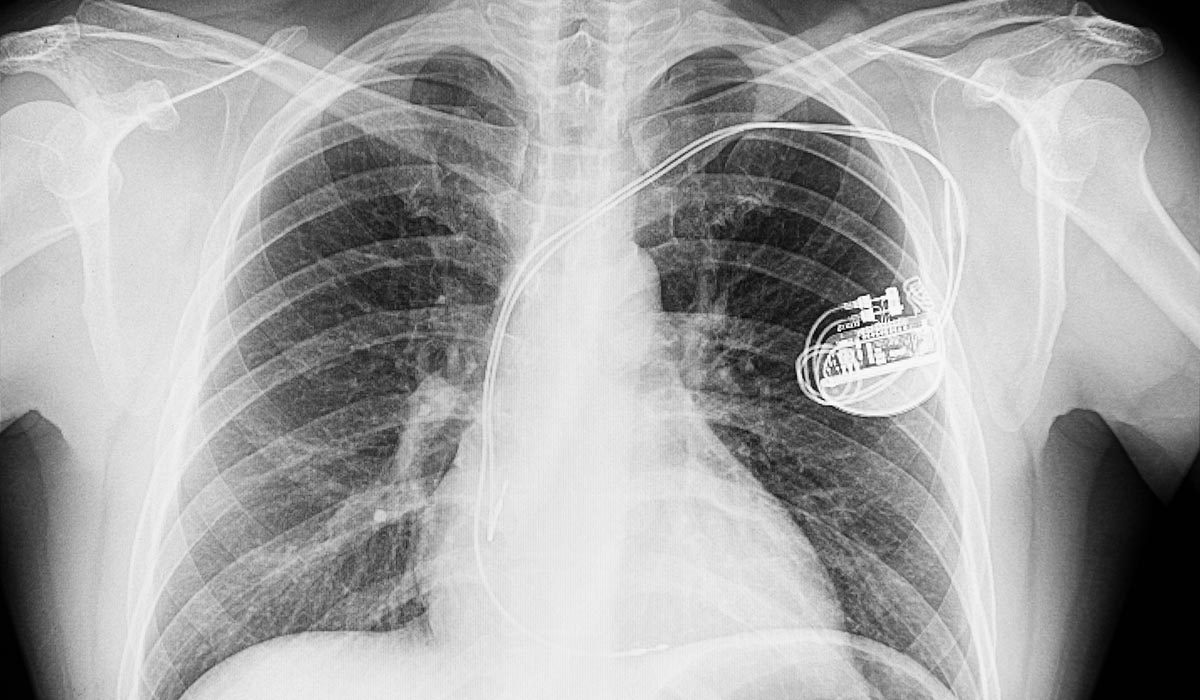

Pacemakers are generally removed before cremation because they are classified as regulated medical waste because they contain bodily fluids. This classification necessitates a meticulous and sterile disposal process.

Thus, why should funeral homes consider the recycling of pacemakers? Beyond their functional significance, numerous pacemaker manufacturers incorporate valuable materials, such as platinum-coated wiring.

While the financial returns from recycling may not be substantial, the broader implications of responsible disposal are considerable. Pacemakers frequently end up in landfills or biohazardous waste containers, contributing to environmental degradation.

By recycling, funeral homes can document their proper disposal, preventing harmful components, such as lithium batteries, from contaminating the ecosystem. This dedication to sustainability enhances the business’s reputation and protects our environment for future generations.